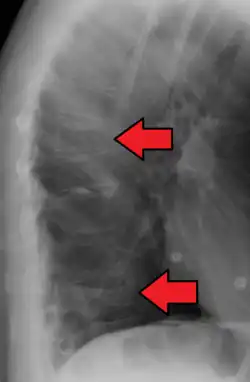

A compression fracture is a collapse of a vertebra. It may be due to trauma or due to a weakening of the vertebra (compare with burst fracture). This weakening is seen in patients with osteoporosis or osteogenesis imperfecta, lytic lesions from metastatic or primary tumors,[1] or infection.[2] In healthy patients, it is most often seen in individuals suffering extreme vertical shocks, such as ejecting from an ejection seat. Seen in lateral views in plain x-ray films, compression fractures of the spine characteristically appear as wedge deformities, with greater loss of height anteriorly than posteriorly and intact pedicles in the anteroposterior view.[3]

Compression fractures are usually diagnosed on spinal radiographs, where a wedge-shaped vertebra may be visible or there may be loss of height of the vertebra. In addition, bone density measurement may be performed to evaluate for osteoporosis. When a tumor is suspected as the underlying cause, or the fracture was caused by severe trauma, CT or MRI scans may be performed.

Compression fracture of T12